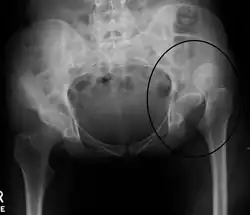

X-ray showing a joint dislocation of the left hip.

An anterior-posterior (AP) X-ray of the pelvis and a cross-table lateral X-ray[24] of the effected hip are ordered for diagnosis.[4][5][16] The size of the head of the femur is then compared across both sides of the pelvis. The affected femoral head will appear larger if the dislocation is anterior, and smaller if posterior.[7] A CT scan may also be ordered to clarify the fracture pattern.[20]